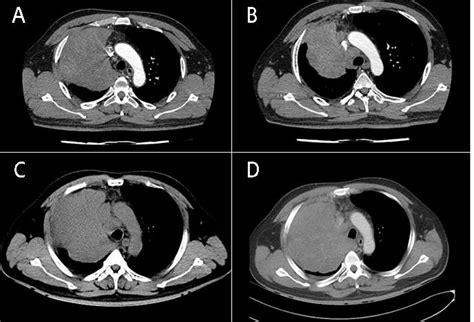

There is currently no singular “standard of care” for Nut Midline Carcinoma due to its rarity, but treatment generally involves a “multimodality” approach. Because the tumor is so aggressive, clinicians often combine several therapies to attempt to achieve disease control. These may include:

• Surgery: If the tumor is localized and surgically accessible, total resection is often the first goal. However, due to the midline location, these tumors are often near critical structures, making complete removal difficult.

• Chemotherapy: Intensive, multi-agent chemotherapy regimens are used to shrink the tumor and treat potential systemic spread.

• Radiation Therapy: High-dose radiation is frequently employed to target the primary tumor site, especially when surgical margins are positive.

• Targeted Therapy: Emerging research into BET inhibitors—drugs that specifically disrupt the proteins created by the NUTM1 fusion—shows promise in clinical trials, though these are typically reserved for refractory cases.